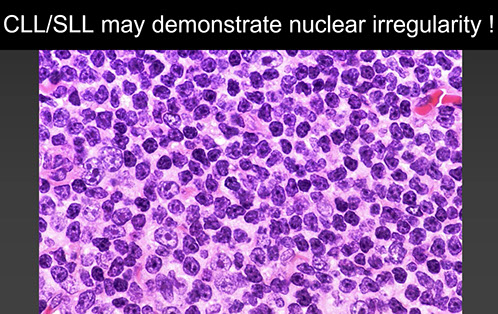

CLL/SLL can show nuclear irregularity